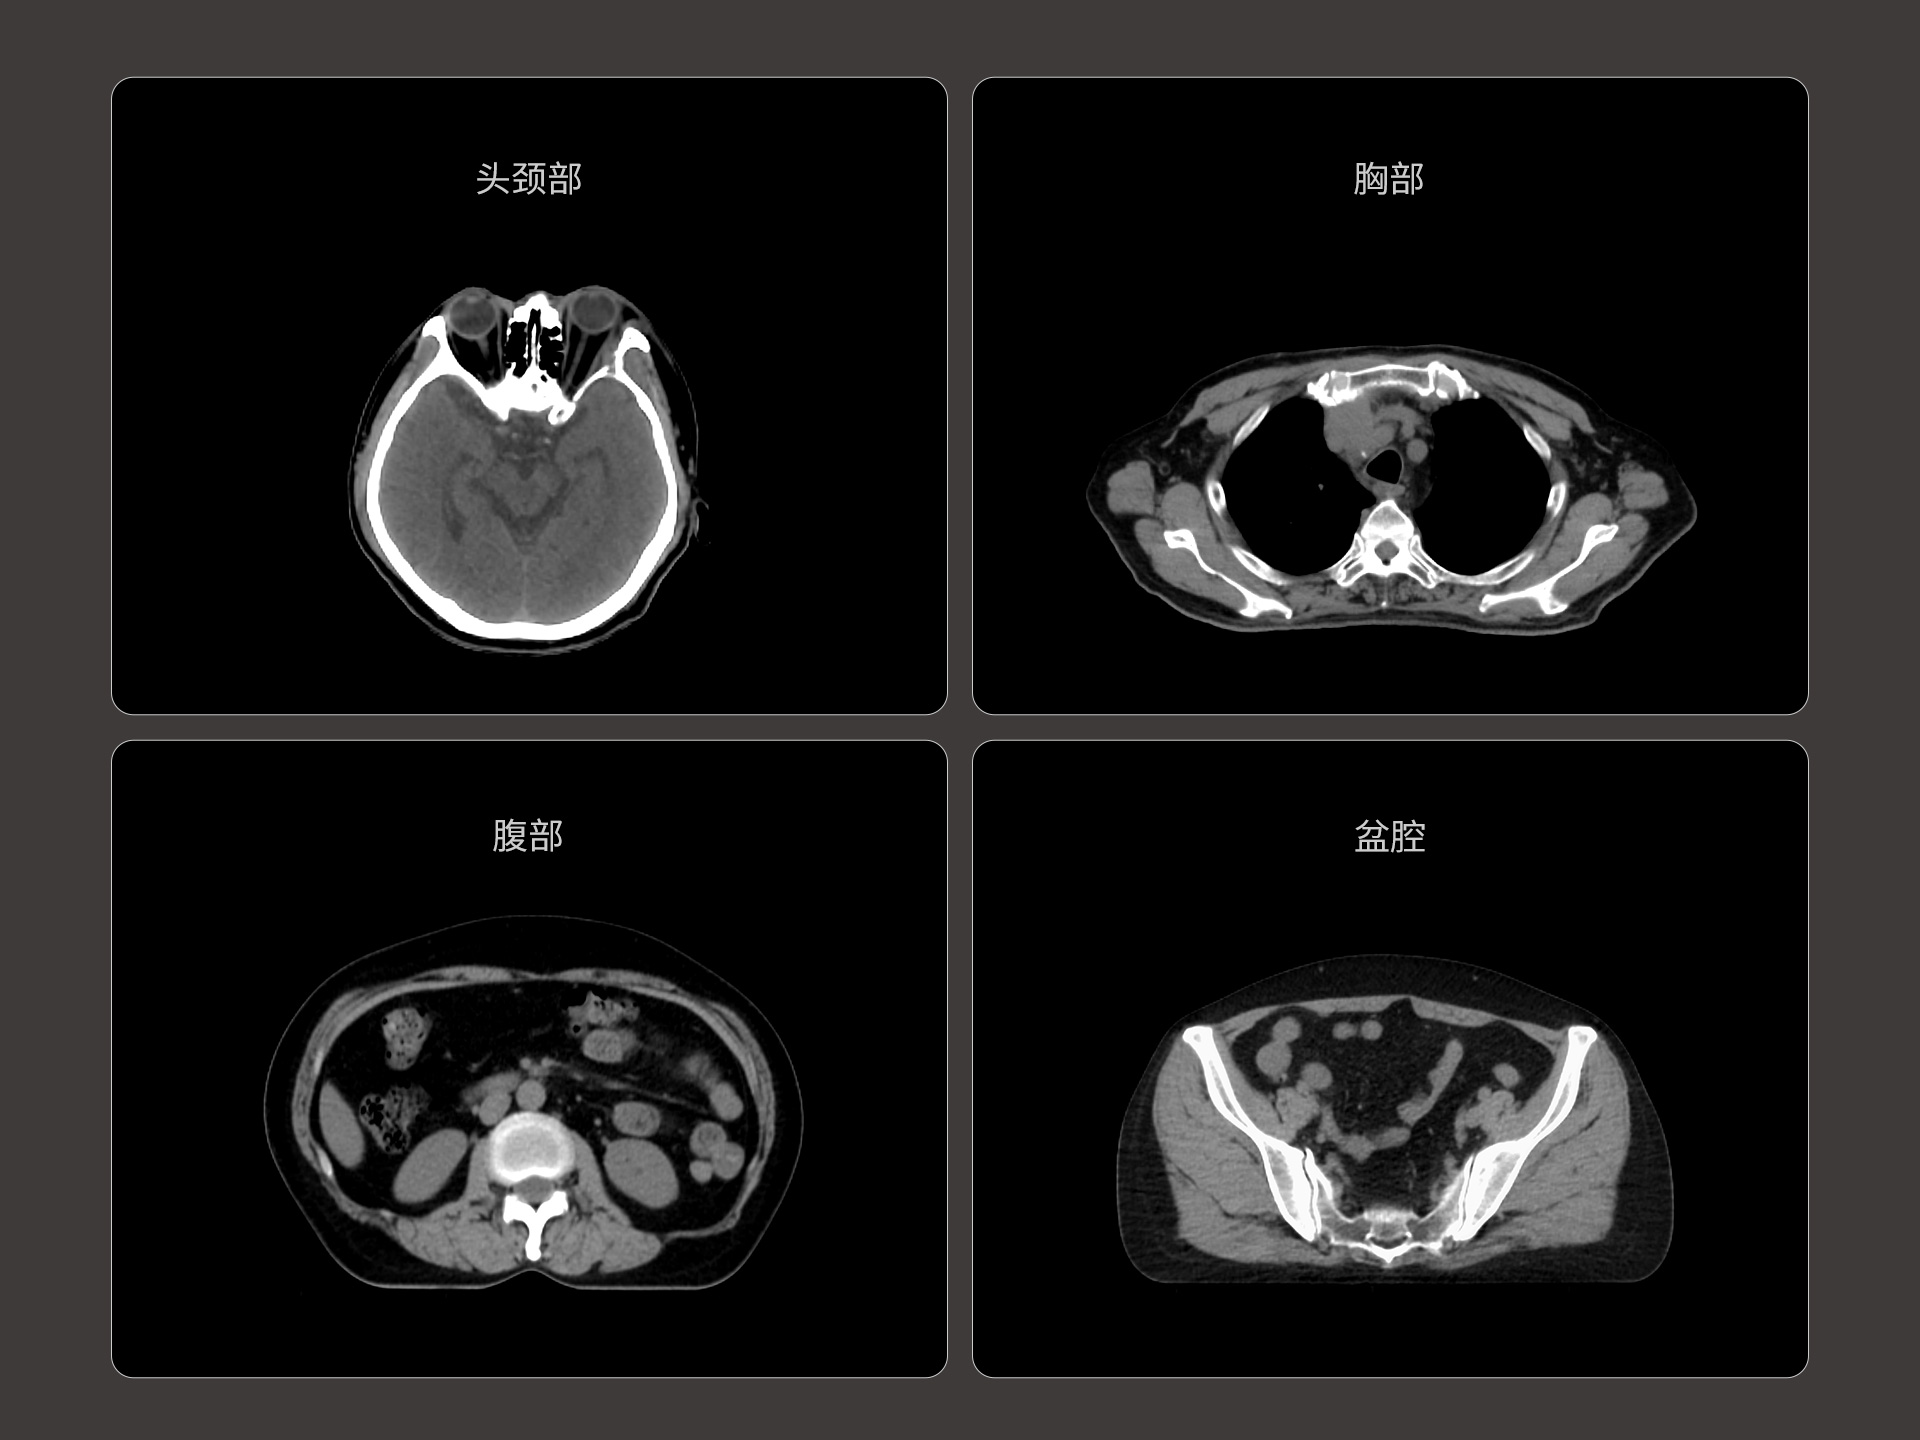

uLinac HalosTx®搭载新一代 87cm 大孔径诊断级CT图像引导系统,全能进阶,实现高清图像质量和全景视野的完美平衡,开辟全疗程 「影像感知」 ,为临床提供更自信、更全面的临床依据。

扇形束成像,极低散射,媲美CT-sim的影像品质

3mm @ 0.3% 高软组织对比度,0.55mm薄层扫描,精确鉴别肿瘤靶区边界

全疗程肿瘤变化感知,加速高清影像引导高水平普及

精准CT值,完美满足勾画、剂量计算要求

从数据源头提升图像质量,高清呈现细微变化,全面精进机载影像实力

提供传统 的CT 模拟机所一致的HU值精度(±10HU)

87cm CT影像孔径设计适配多种摆位姿势,兼顾不同体型患者

标准视野 63cm,避免扫描信息缺失

轴向视野 91cm,轻松实现长靶区扫描

0.37s/360° 旋转速度,减少运动伪影,大幅提高时间分辨率

4D CT 动态肿瘤追踪,运动靶区精准勾画

低剂量CT,保证成像质量的同时降低患者辐射剂量